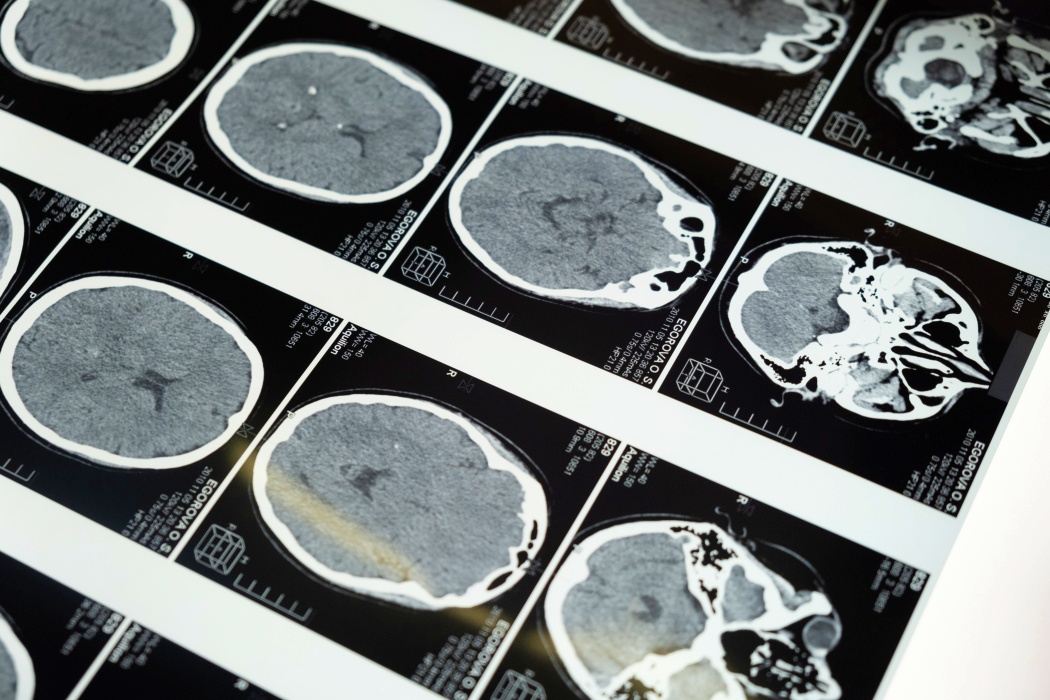

A stroke korunk egyik vezető haláloka, és a leggyakoribb rokkantsághoz vezető betegség, amely csak hazánkban mintegy 40.000-50.000 beteget érint évente, és több mint harmaduknál válik végzetessé. A stroke hátterében az esetek több mint 85%-ában az agyat vérrel ellátó ér elzáródása áll, 15% pedig agyvérzés következtében alakul ki.